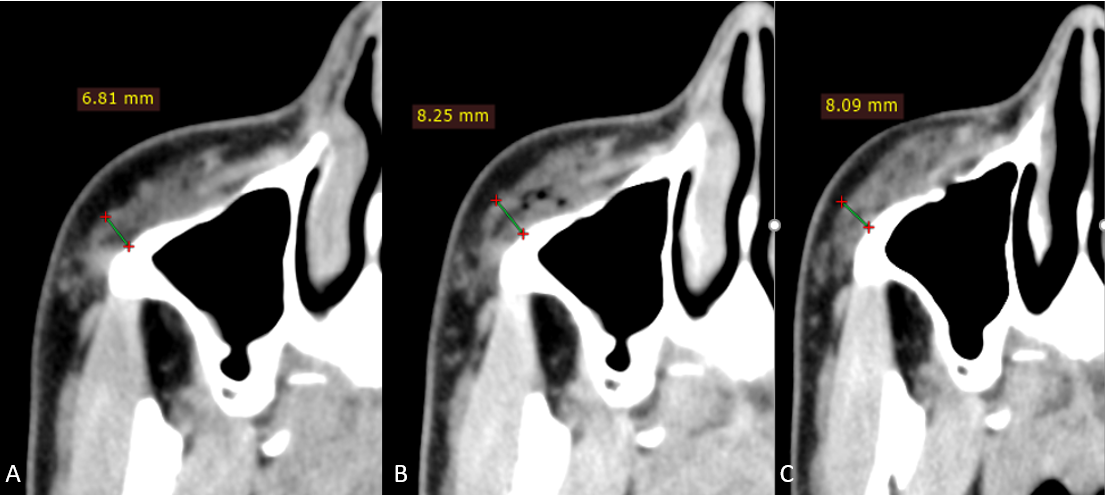

Данные МСКТ (рис.5,6): на аксиальном срезе скуловой области до инъецирования определяется ранее введенный имплантат в виде болюсов плотностью, аналогичной плотности мышечной ткани, толщиной справа 6,8 мм, слева 4,7 мм, прилегающих к передним стенкам верхнечелюстных пазух. В динамике после введения и через 21 день визуализируется увеличение толщины болюсов до 8,1мм справа и 7,9мм слева, миграции препарата в окружающие мягкие ткани, реактивных изменений окружающих структур и признаков инкапсулирования к 21 дню не выявлено, также определяется появление более четких контуров, формирование гомогенной структуры и нивелирование инфильтративных изменений ПЖК посттравматического характера.

Рисунок 5

МСКТ сканы правой скуловой области, аксиальная проекция

А – до инъецирования, толщина имплантата 6,8 мм

В – сразу после инъецирования, толщина имплантата 8,3 мм

С – через 3 недели, толщина имплантата 8,1 мм

Рисунок 6

МСКТ сканы левой скуловой области, аксиальная проекция

А – до инъецирования, толщина имплантата 4,7 мм

В – сразу после инъецирования, толщина имплантата 8,0 мм

С – через 3 недели, толщина имплантата 7,9 мм